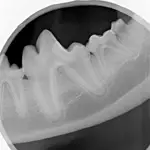

After the patient is anesthetized using multimodal pain control protocol (including a mandibular nerve block), obtain an intraoral radiograph to evaluate root structure and mandibular bone integrity.